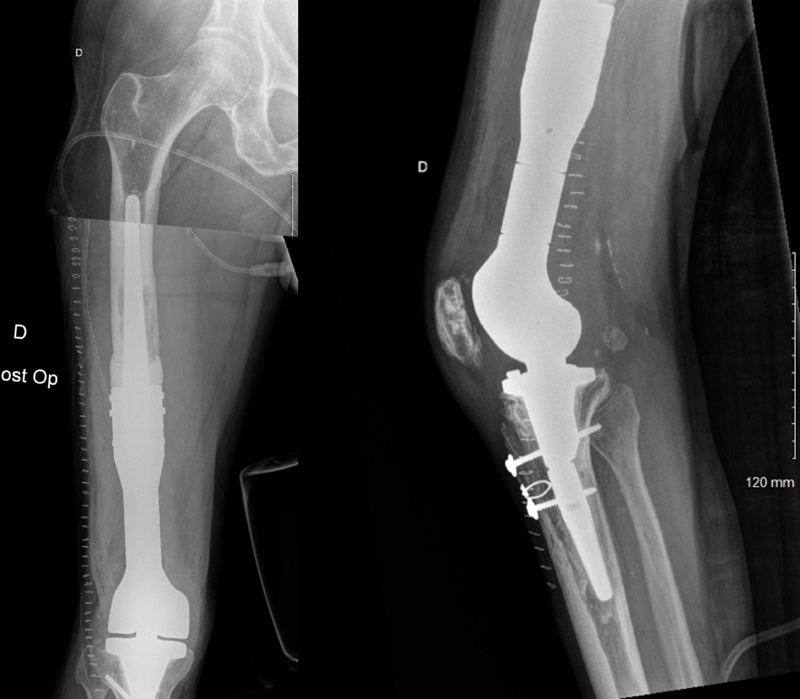

Post-operative X-Rays

• Removal of the broken metaphyseal component

• Preservation of the femoral stem

• Use of custom-made Implant RescueSleeve MEGASYSTEM-C (LINK® society)

• The objective was to choose the less morbid strategy allowing the preservation of a good femoral fixation and maximal bone saving.

Major femoral osteolysis was noticed on distal femoral shaft until approximately the second steel strapping. This femoral height level was chosen to do the femorotomy. The remaining femoral stem was then tested and appeared to be perfectly sealed.

The appropriate size of the custom-made Implant RescueSleeve MEGASYSTEM-C (LINK® society) was then tested and chosen. The sleeve was cemented around the remaining femoral stem and fixed with 16 specific screws.

The prosthesis was then reconnected to the tibial component.